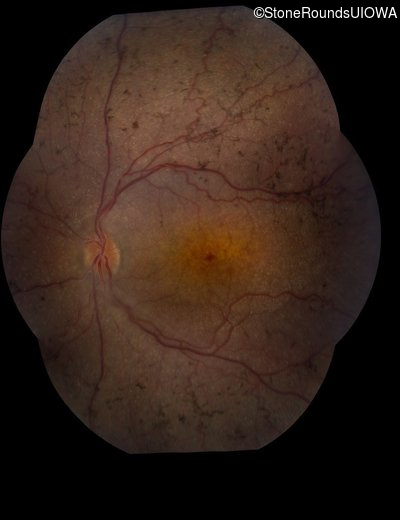

Fundus Montage - Right - 10/300

Exemplar